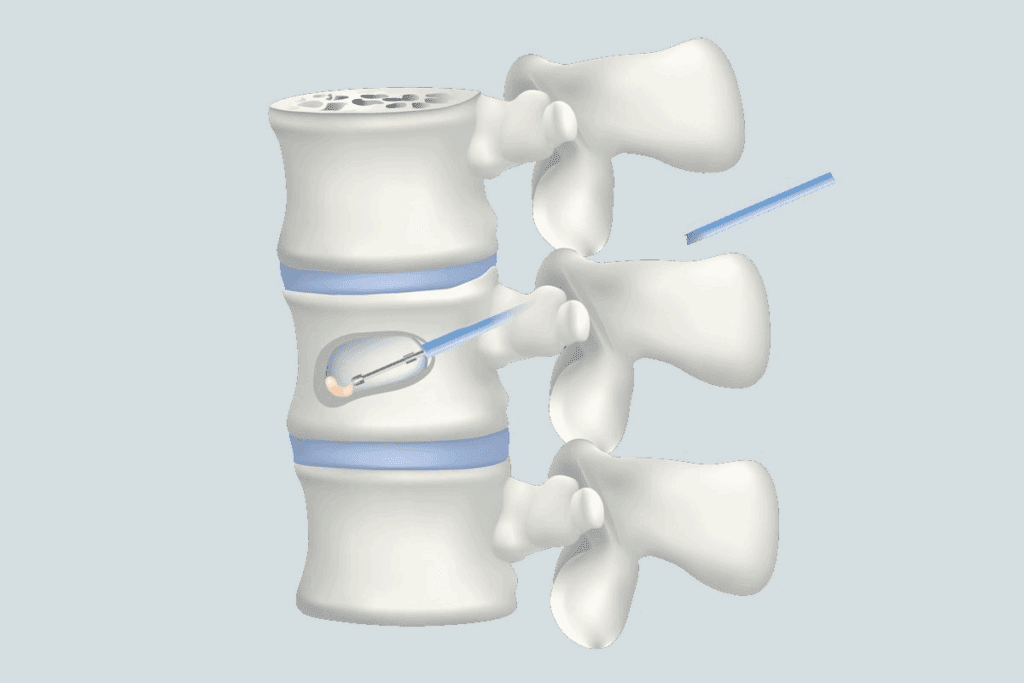

Epidural steroid injections are a helpful treatment for L5 S1 disk protrusion. They aim to reduce inflammation and ease pain in the lower back and legs. Let’s dive into how these injections work and their benefits for L5 S1 disk protrusion.

Epidural steroid injections put anti-inflammatory medicine near the spinal cord. This method helps lessen swelling and irritation around the nerves. It can greatly reduce pain and improve movement for those with L5 S1 disk protrusion.

The procedure is done under X-ray to ensure the medicine goes exactly where it needs to. Patients lie on their stomach, and the area is cleaned and numbed. Then, a thin needle injects the medicine into the epidural space.

Most people can go back to normal activities a few hours after. Some might feel sore at the injection site. Relief can start in a few days or take up to two weeks for some.